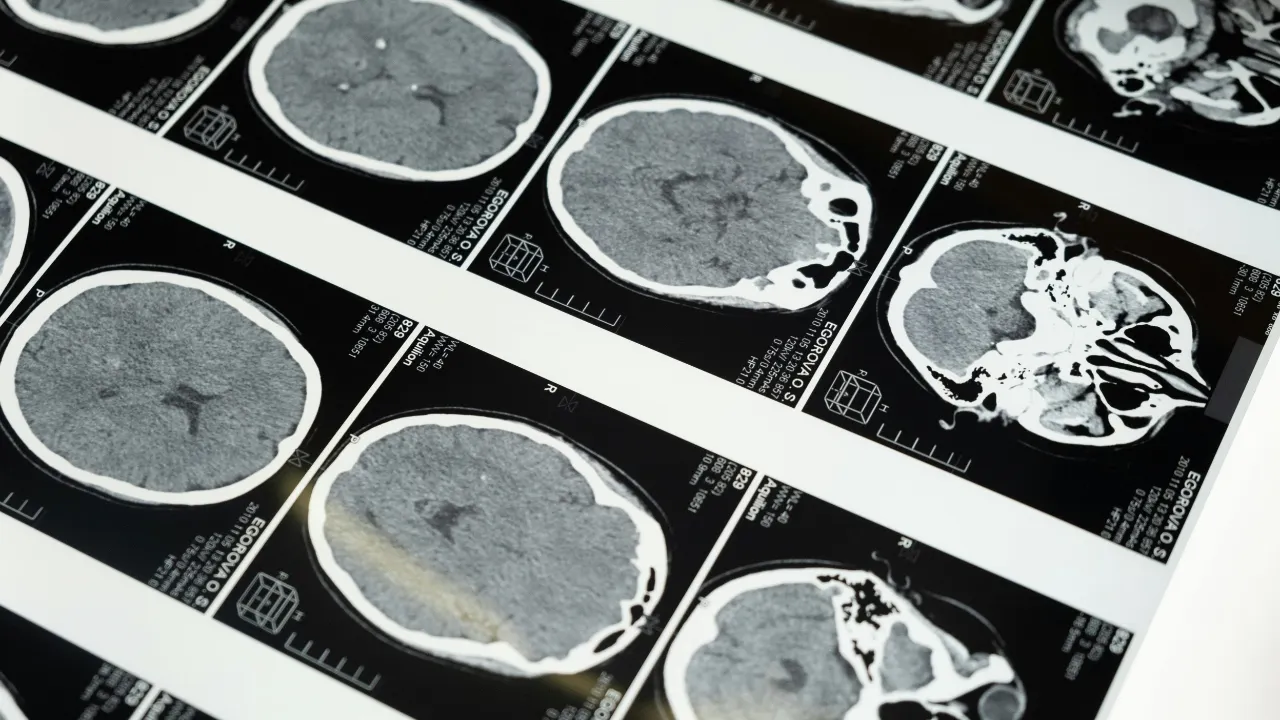

Typically, brain-computer interfaces rely on electrodes to measure electrical signals from neurons—think of Neuralink, for instance, which uses tiny threads implanted in the brain. Ultrasound technology takes a different approach.

- Create detailed internal images

- Target and eliminate abnormal cells like tumors

- Modulate neural activity without open surgeries